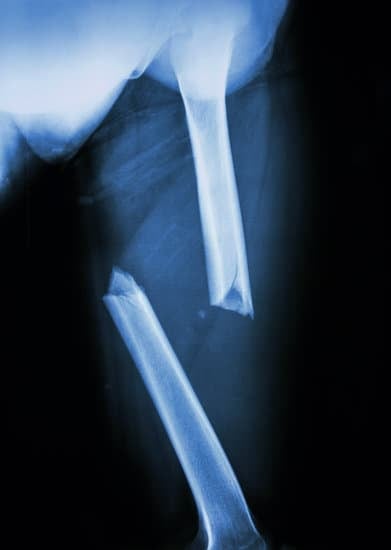

대퇴골 골절 수술 방법에 대한 이해

대퇴골 골절은 특히 노인 인구에서 발생률이 높은 중대한 부상으로, 이는 이동 능력에 심각한 영향을 미칠 수 있습니다.

이러한 골절은 낙상, 교통사고 또는 높은 에너지가 작용하는 다양한 사고로 인해 발생할 수 있습니다.

대퇴골 골절의 치료는 골절의 종류, 환자의 나이, 전반적인 건강 상태 및 골절이 발생한 대퇴골의 위치에 따라 달라질 수 있습니다.